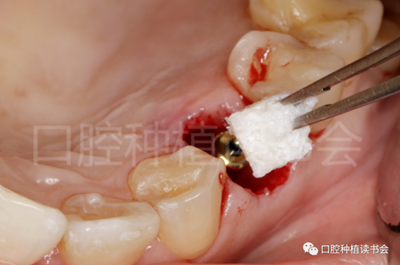

5.3.4  旋入覆蓋螺絲,在種植體與四周骨壁的間隙內(nèi)植入 Bio-Oss Collagen,植骨材料用生理鹽水濕潤后,用15#刀片分割為小塊分別植入,并用充填器壓實(shí)(圖17)。

后牙區(qū)即刻種植臨床指南

圖17 后牙即刻種植植骨推薦使用骨膠原材料,有利于軟組織愈合。